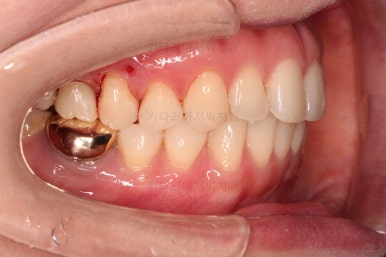

마찬가지로 부산치아교정비용 초진 시 입안의 모습입니다.

아랫니가 많이 보이지 않는 타입이라서 잘 몰랐는데 입안을 관찰해 보니 아래 앞니가 삐뚤어 있네요.

이 부분도 꼭 교정해야 될 정도는 아니여서 선택의 문제라고 할 수 있는데요.

어금니가 문제였습니다.

윗니 어금니가 하나 없는 상태였고요.

어금니가 없이 지낸지 꽤 시간이 흐른터라 뒤쪽 어금니가 앞으로 쓰러져 공간을 잠식하고 있었습니다.